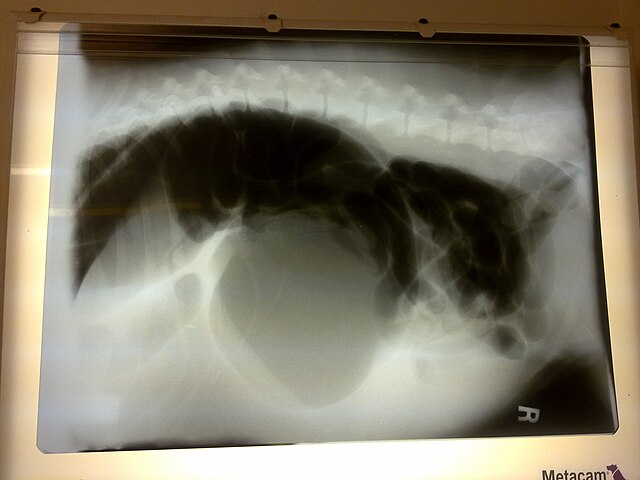

Case Study #42 • GIT Surgery

Gastric Volvulus (GDV)

Master the emergency flow. From decompressing the stomach to the final gastropexy decision.

X-Ray Indicators

Image: Cokehabit (CC BY-SA 3.0)